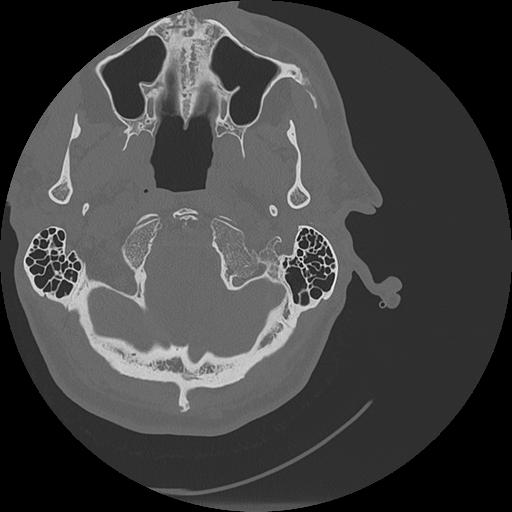

7 HUESO,,Vol,0.5,HUESO,,